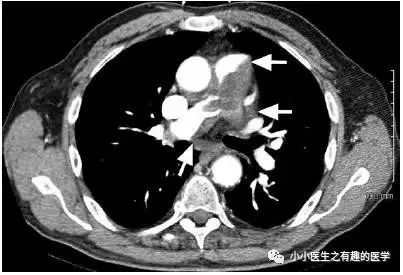

文献七

里约热内卢联邦大学。

35岁女性,呼吸困难,咯血,胸痛。哈哈,典型的肺栓塞。

绝对的肺栓塞。诊断慢性肺栓塞,治疗6月。

复查:

星星,还是那颗星;月亮,还是那个月......,血栓,还是那么大滴哟,一个——血——栓。还来不及手术,患者died。

A significant clinical worsening was observed and the patient died before she could be submitted to a diagnostic/therapeutic surgical procedure.

最终诊断:肺动脉肉瘤。